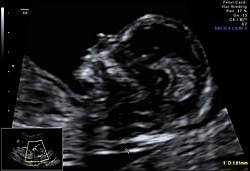

Die Untersuchung ist eine Kombination aus einer Ultraschalluntersuchung (First-Trimester-Screening) mit Darstellung von Nackentransparenz, Nasenbein und anderer Ultraschallmarker kindlicher Chromosomenstörungen, sowie einer Bestimmung zweier Hormone im mütterlichen Blut:( APP-A und freies ß-HCG.

Das First-Trimester-Screening mit Nackenfaltenmessung sollte jedoch auch nach einem Harmony Test durchgeführt werden. Denn es können trotz unauffälligem NIPT Test eine erhöhte Nackentransparenz oder andere kindlichen Auffälligkeiten vorliegen. Es muss jedoch nach einem NIPT keine Risikoberechnung und Hormonbestimmung mehr durchgeführt werden.

Beim First-Trimester-Screening werden folgende Strukturen untersucht:

Bei einer ausgeprägten Nackenfalte über 3,5 mm oder Fehlbildungen im Ultraschall wird zusätzlich eine noch genauere genetische Untersuchung (Microarrays) angeschlossen.